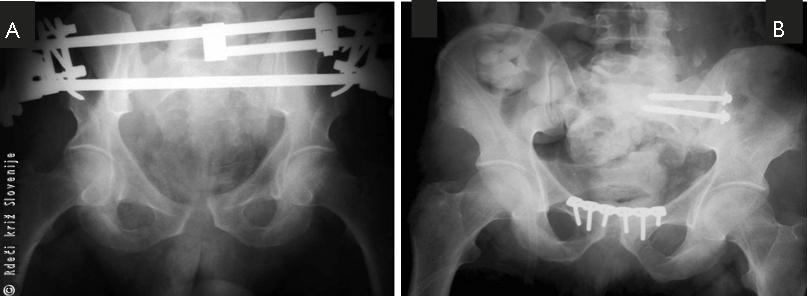

Slika 8

A – RTG medenice po začasni urgentni oskrbi z zunanjim fiksatorjem.

B – Po dokončni notranji učvrstitvi.

Medenični obroč je bil začasno učvrščen z zunanjim fiksatorjem, napravljena je bila tudi laparotomija (pregledna operacija trebuha) in ustavljena krvavitev iz mezenterija tankega črevesa. Po začetni oskrbi je bil poškodovanec hemodinamsko stabilen. Dokončna učvrstitev medenice je bila napravljena peti dan po poškodbi. Poškodovančevo dokončno zdravljenje je potekalo brez zapletov. Tri mesece po poškodbi se je vrnil k vsem normalnim dejavnostim.